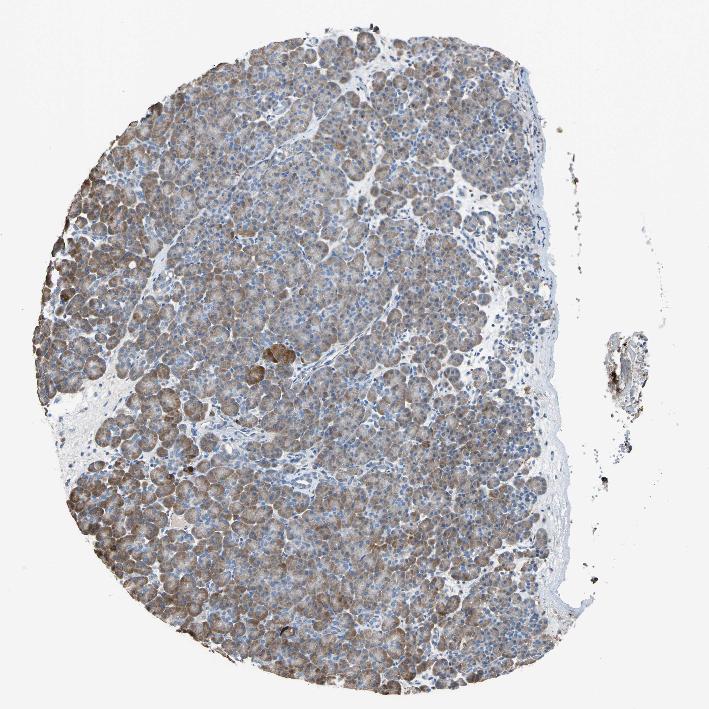

PANCREAS - Antibody stainingi

Antibody staining in the annotated cell types in the current human tissue is reported as not detected, low, medium, or high, based on conventional immunohistochemistry profiling in selected tissues. This score is based on the combination of the staining intensity and fraction of stained cells.

Each image is clickable and will lead to virtual microscopy that enables deeper exploration of all samples and also displays staining intensity scores, fraction scores and subcellular localization as well as patient and tissue information for each sample.

Antibody HPA005824

Exocrine glandular cells Medium

Pancreatic endocrine cells Low